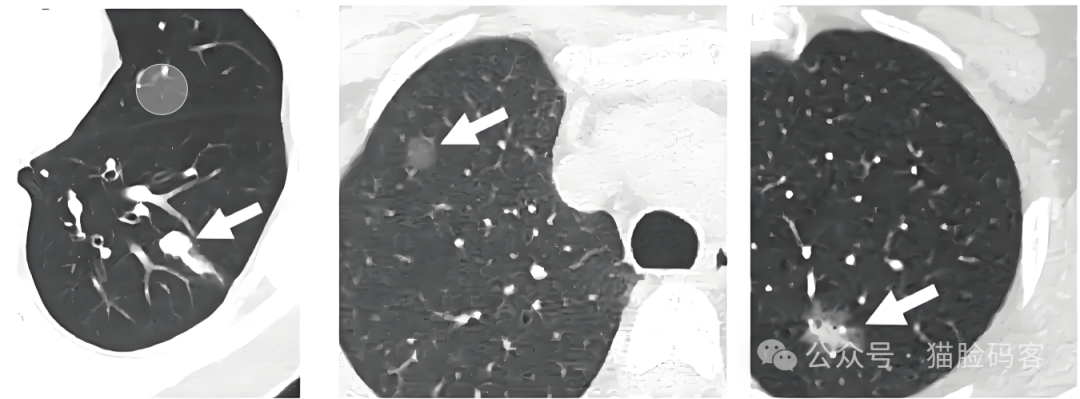

在医学影像诊断领域,CT技术以其高分辨率、无创检测以及三维重建等独特优势,在肺部疾病的筛查与诊断中发挥着举足轻重的作用。肺结节作为肺部常见的异常病变之一,其形态多样、大小不一,且可能隐藏在复杂的肺部结构中,给医生的诊断带来了不小的挑战。传统的肺结节检测方法主要依赖于医生的肉眼观察与经验判断,这不仅耗时费力,而且易受主观因素影响,导致诊断结果的准确性和一致性存在波动。因此,研究肺结节CT图像的分类与分割技术,实现肺结节的自动化检测与精准识别,对于提高诊断效率、减轻医生工作负担以及促进肺部疾病的早发现、早治疗具有重要意义。

目前,肺结节CT图像的分类与分割技术已取得了一定的研究进展。传统的图像处理方法,如阈值分割、区域生长、形态学处理等,在肺结节分割方面具有一定的效果。这些方法主要基于图像特征提取和分类器设计,通过设定特定的阈值或规则来区分肺结节与周围组织,从而实现分割目的。然而,这些方法易受噪声、伪影等因素影响,导致分割结果的准确性和鲁棒性受限。

近年来,随着深度学习技术的兴起和快速发展,卷积神经网络(CNN)等深度学习模型在肺结节分类与分割中展现出了强大的性能。深度学习模型通过构建深层次的神经网络结构,能够自动学习图像中的复杂特征表示,实现对肺结节的精准识别与分割。相比传统方法,深度学习方法在肺结节分类与分割中取得了显著优于传统方法的性能。然而,现有方法仍存在一些问题和挑战。例如,深度学习模型的复杂度较高,需要大量的计算资源和训练数据来支持模型的训练和推理过程。此外,现有方法在处理复杂背景、多尺度结节以及结节与周围组织边界模糊等方面仍存在困难。因此,如何优化深度学习模型,提高其在肺结节分类与分割中的性能和泛化能力,是当前研究的重要方向。